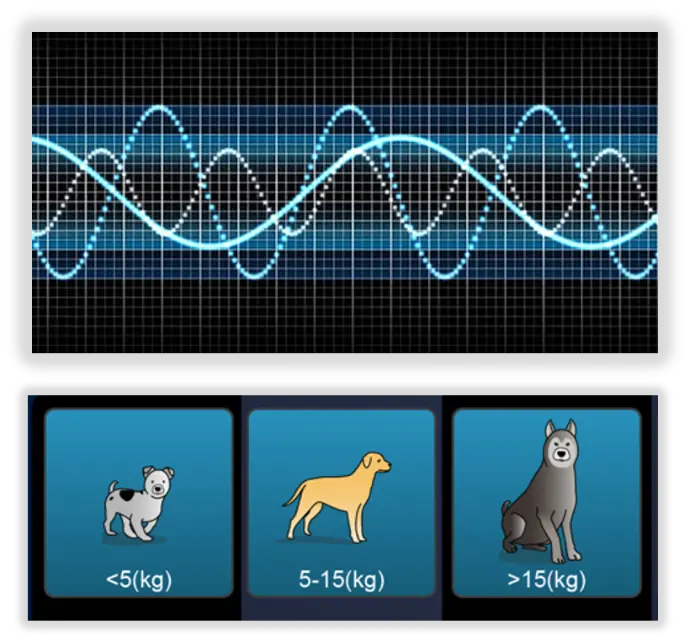

Специални Vet пресети на изобржежението

Предварително зададени професионални ветеринарни настройки на изображението според различните видове животни (кучета, котки, говеда, овце и персонализирани видове)

Животните се категоризират по тегло и размер на тялото, за бърза, прецизна и лесна диагностика.

Dedicated Veterinary Image Presets

Preset exams according to different animals body characteristics (canine, feline, equine, bovine, ovine and customized species )

Animals are subdivided to different categories by weight and body size

(Dog: <5 kg. 5 15 kg. >15 kg. ) for precise and easier diagnosis.